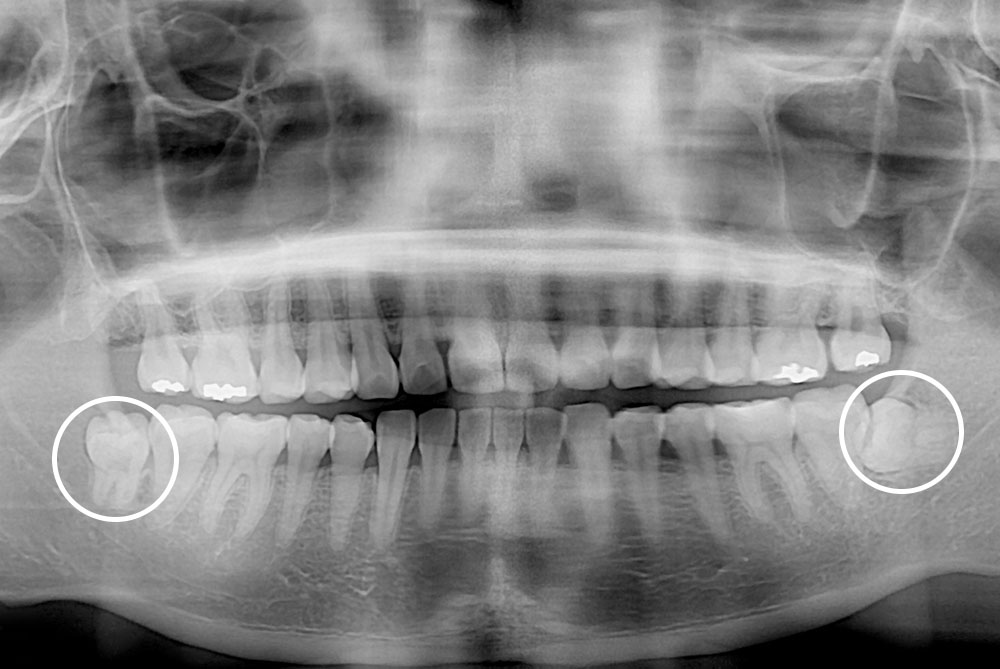

[사랑니] 매복 사랑니 발치

치료후 : 2019-12-16